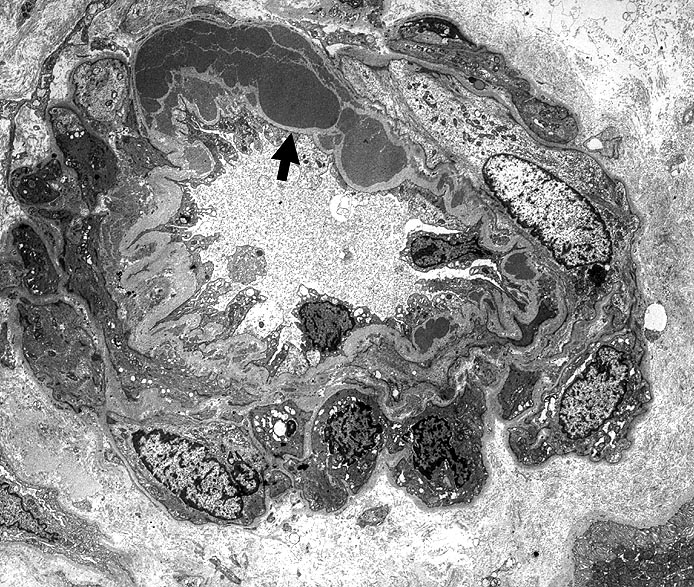

Innerhalb der Basalmembran gelegene plumpe ► Proteinablagerungen. Die glatten Muskelzellen sind in der gesamten Peripherie erhalten.

Typisch für Diabetes mellitus ist der Befall von Vas afferens und efferens, oft auch der Vasa recta. In intrarenalen Arterien unspezifische Atherosklerose teilweise mit Atheromen (typisch für Diabetes). Der Schweregrad korreliert im allgemeinen mit dem Ausmass der exsudativen Läsionen der Glomerulosklerose. Die Arteriolosklerose im Vas afferens beim Diabetes ist identisch mit der Arteriolosklerose bei arterieller Hypertonie.